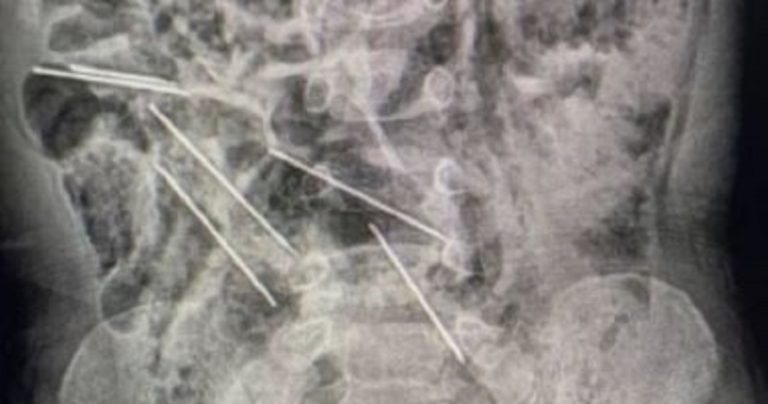

طفل يبتلع 8 إبر حقن!